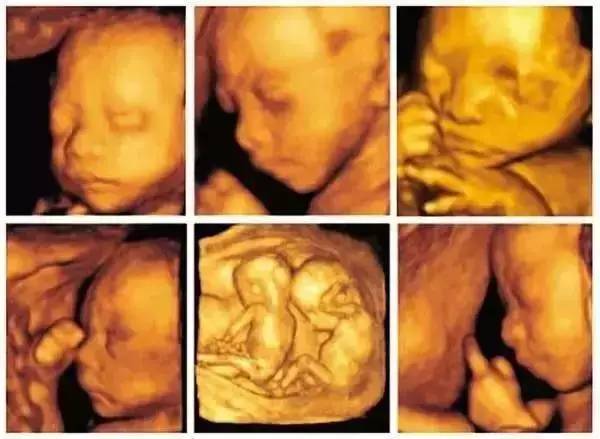

四維彩超下的睪丸圖像

通過(guò)四維彩超技術(shù),我們可以清晰地觀察到睪丸的內(nèi)部結(jié)構(gòu),在四維彩超圖像上,睪丸通常呈現(xiàn)為一種均勻的回聲結(jié)構(gòu),其中可以看到細(xì)小的血管、淋巴管和神經(jīng),還可以觀察到睪丸內(nèi)的睪丸實(shí)質(zhì)和附睪等結(jié)構(gòu),這些結(jié)構(gòu)的清晰可見(jiàn)有助于醫(yī)生進(jìn)行準(zhǔn)確的診斷。